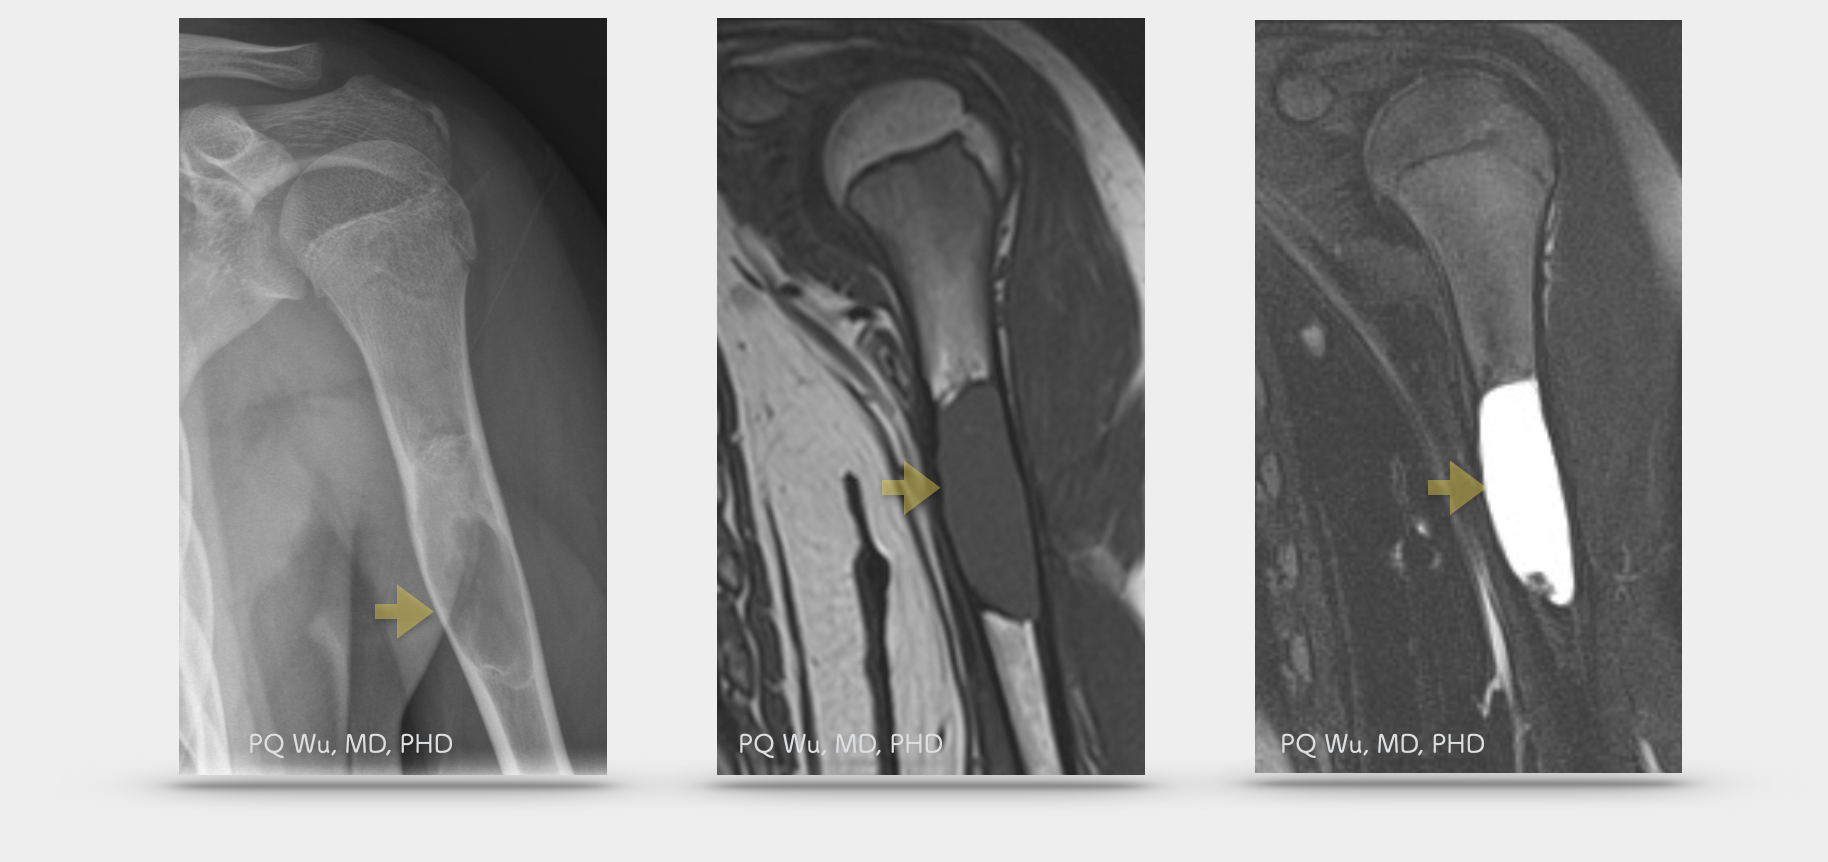

影像學中,在X光下單純性骨囊腫多生長在骨頭中間(central location),會造成骨頭些許的膨漲(mild expansion)。除非有病理性骨折,否則不會發生骨膜反應(peiosteal reaction)。更不會破出骨骼外而侵犯周遭軟組織。在MRI中,可以在T1訊號中發現有均勻的中度訊號在病灶之中(homogeneous intermediate signal intensity)。而在T2訊號中發現有均勻高強度訊號在病灶之中(homogeneous high signal intensity)。這些都是單純性骨囊腫典型的影響學發現。

X光,造成骨膨漲的骨囊腫 (上圖左)。MRI (T1),均勻的中度訊號於病灶中(上圖中)。MRI (T2),均勻高強度訊號於病灶中(上圖右)。